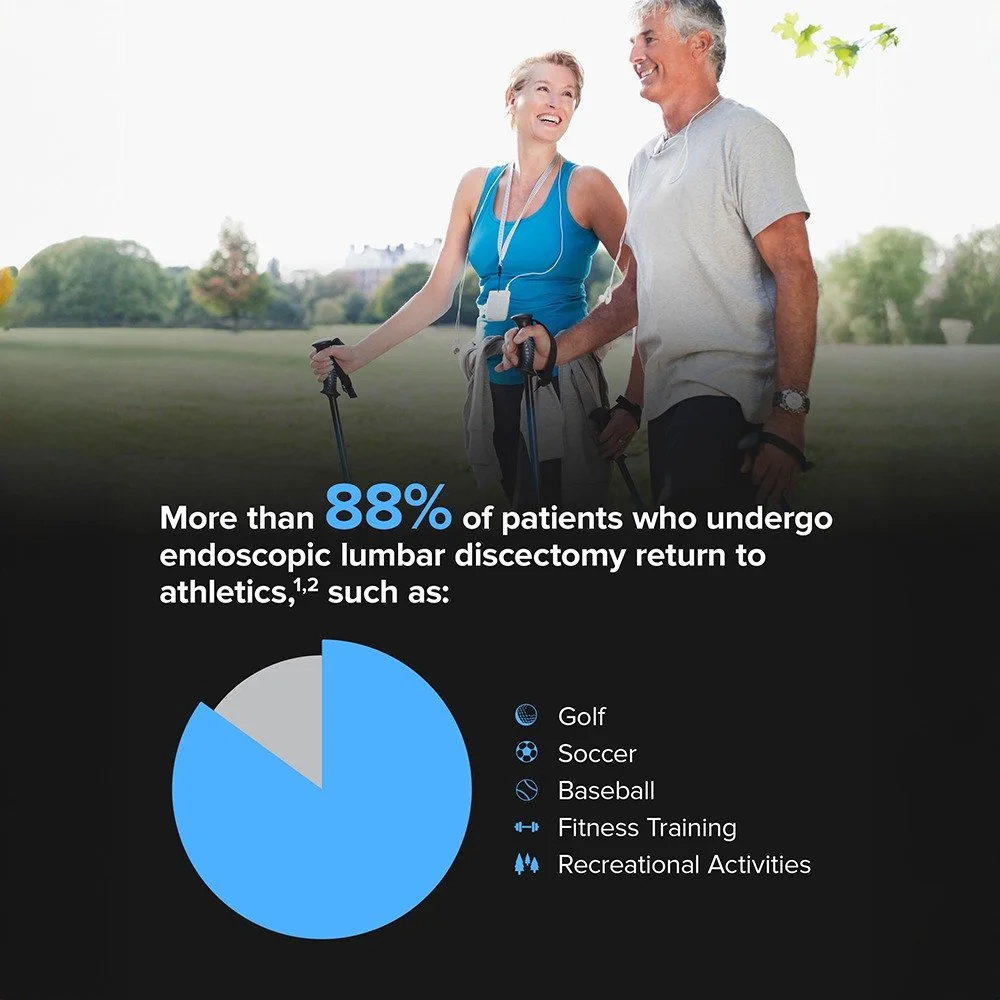

Specializing in minimally invasive spine surgery to get you better and back to your life

Spinal Treatments